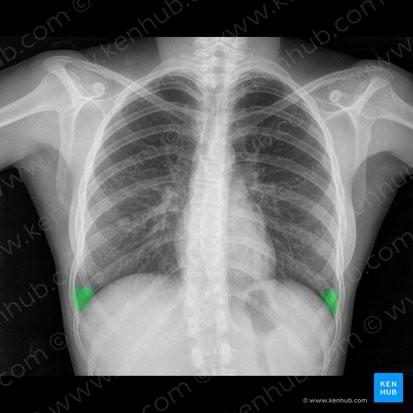

Radiografía de tórax: índice cardiotorácico normal, hilios engrosados con adenopatías calcificadas. Silueta cardiomediastínica y parénquimas sin otros hallazgos.